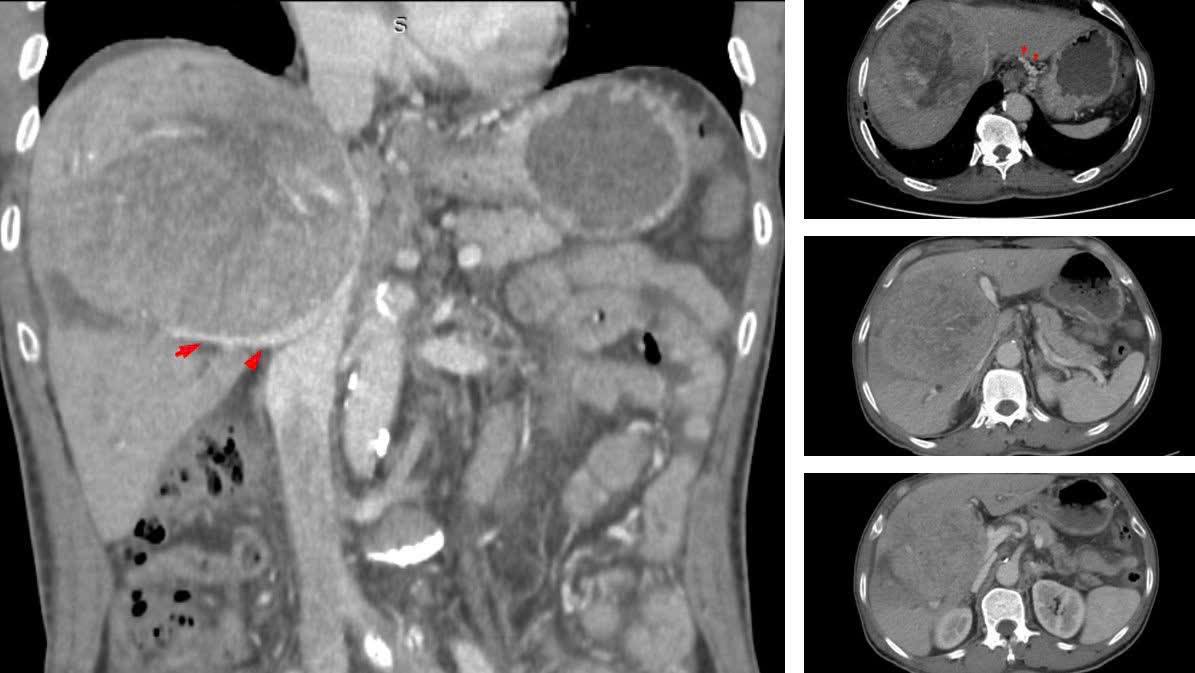

Chỉ đến khi triệu chứng rõ ràng, bệnh nhân mới đi kiểm tra, khối u gan đã phát triển với kích thước khổng lồ từ 10–12 cm. Tại một số cơ sở y tế, ông từng được tiên lượng thời gian sống không quá 9 tháng.

Tháng 7/2023 bệnh nhân có khối u gan kích thước lớn.

BSCKII Nguyễn Trường Giang, Phó Giám đốc Trung tâm Phẫu thuật Gan mật – Tiêu hóa (Bệnh viện Bệnh Nhiệt đới Trung ương) cho biết, khi nhập viện, đây là ca bệnh rất nặng. Khối u lớn chiếm gần hết nhu mô gan, chèn ép rốn gan và các mạch máu, gây cổ chướng nhẹ và phù hai chi dưới.